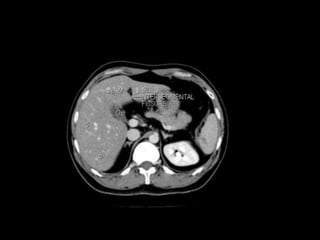

Right hepatic veindivides the right lobe into anterior and posterior segments. Middle hepatic vein divides the liver into right and left lobes (or right and left hemiliver).This plane runs from the inferior vena cava to the gallbladder fossa. The Falciform ligament divides the left lobe into a medial- segment IV and a lateral part - segment II and III. The portal vein divides the liver into upper and lower segments. The left and right portal veins branch superiorly and inferiorly to project into the center of each segment. Anatomy of liver segments

segment I :is the caudate lobe situated posteriorly around the IVC and different to the other 7 segments. It may receive its supply from both the right and the left portal vein and is drained directly into the IVC by one or more small hepatic veins The remainder of the segments (II toVIII) are numbered in a clockwise fashion starting superiorly in the left hemiliver : segments II and III : are lateral to the left hepatic vein and falciform ligament with II superior and III inferior to the portal plane segment IV : lies medial to the falciform ligament, between the left and middle hepatic veins. It is subdivided into IVa (superior) and IVb (inferior) subsegments. Easy tip: IVa above and IVb below the portal plane. Segment IV includes the quadrate lobe. SegmentV toVIII make up the right hemiliver and are easier to describe: segmentV : is located below the portal plane between the middle and right hepatic veins segmentVI : is located below the portal plane lateral to the right hepatic vein segmentVII : is located above the portal plane lateral to the right hepatic vein segmentVIII : is located above the portal plane between the middle and right hepatic veins